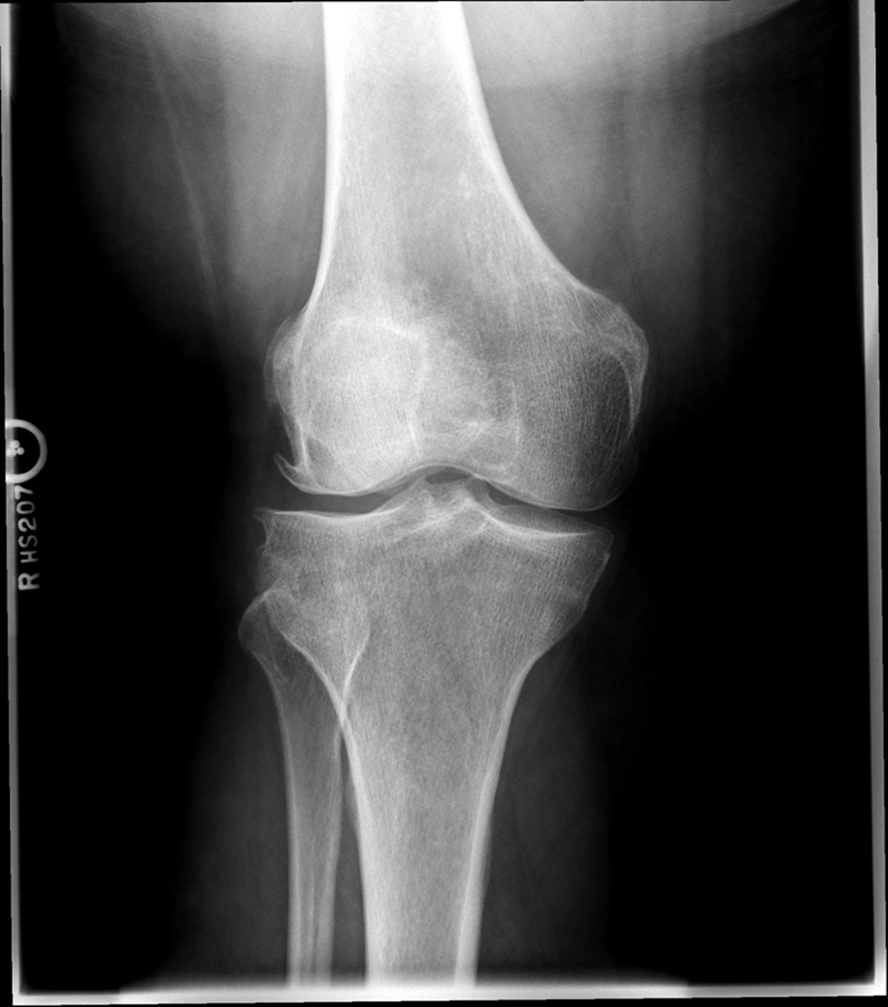

Osteoarthritis

(Degenerative Joint Disease)

Generalized disorder pathologically characterized by loss of joint cartilage and reactive new bone formation.

Cause: traumatic, stress to joints

Complications: joint pain, stiffness, trouble using joints for walking, grasping, etc

Radiographic Appearance: irregular narrowing of joint spaces and development of small bony spurs (osteophytes)

•Knee – articular ends become increasingly dense and joint narrowing is asymmetric

•Fingers – affect distal joints, marginal spurs produce well defined bony protuberances (can palpate and see knobby appearance)

•Hip – asymmetric narrowing of joint space (superiorly and laterally)

Technical: Advance Stage – Subtractive disease

•May require slight decrease

Prognosis: Some patients are unaffected by osteoarthritis while others can be severely disabled.

•Joint replacement surgery for some results in the best long-term outcome.